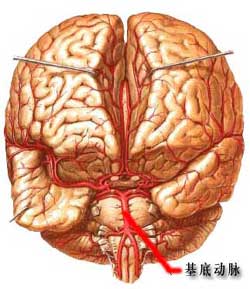

腦性癱瘓--分析圖由於病因不同其病理改變亦不甚相同。常見的病理改變為腦發育不全,大腦皮質萎縮,神經細胞數目減少,皮質下白質萎縮,深部結構的膠質細胞增生,大腦半球半卵圓中心囊性變,腦室旁軟化,蒼白球及視丘下核可見脫髓鞘改變。另外肉眼可見腦瘢痕、軟化、硬化、萎縮、腦積水等。